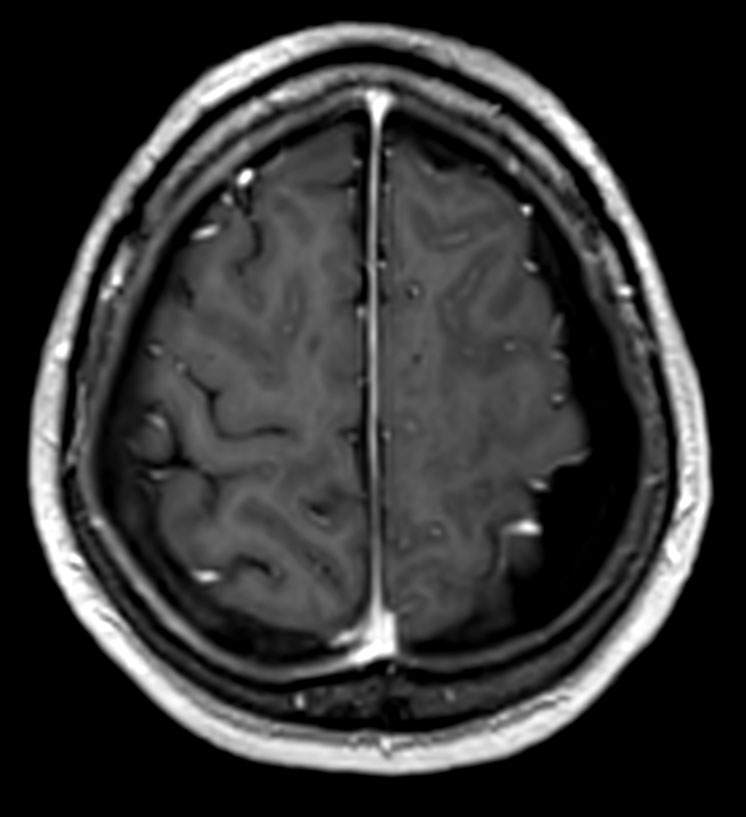

Axial 3D T1W FFE post contrast